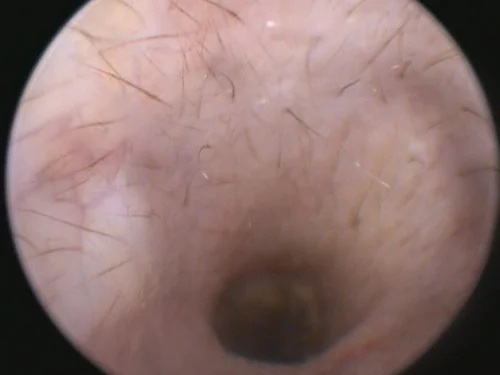

Video otoscopy has revolutionized the treatment of ear infections by our medical team as it provides amazing clarity to assess the condition of the ear canal, eardrum, and, at times, the middle ear.

Video otoscopy is the use of a small rigid otoscope with a camera built in that can be passed into the ear canal. The image is then projected onto a screen allowing magnification and much greater clarity to observe the deeper ear canal and structures.

Small channels within the otoscope also allow instruments to be passed into the ear canal to facilitate deeper cleaning, polyp or tumor removal, and other procedures. The use of video otoscopy in a challenging ear case is often the difference between months of continued struggles and a much more rapid resolution of infection and disease.